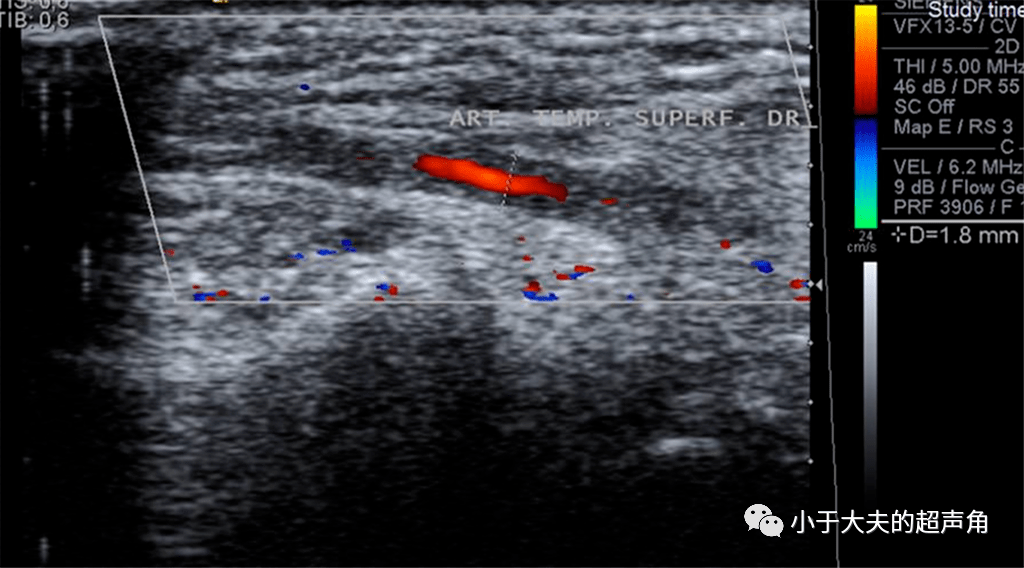

图9颞动脉炎.png

超声随响〗第75期 颞动脉炎和晕环征 halo sign

颞动脉炎是巨细胞性动脉炎的一种,巨细胞性动脉炎主要影响颈外动脉的